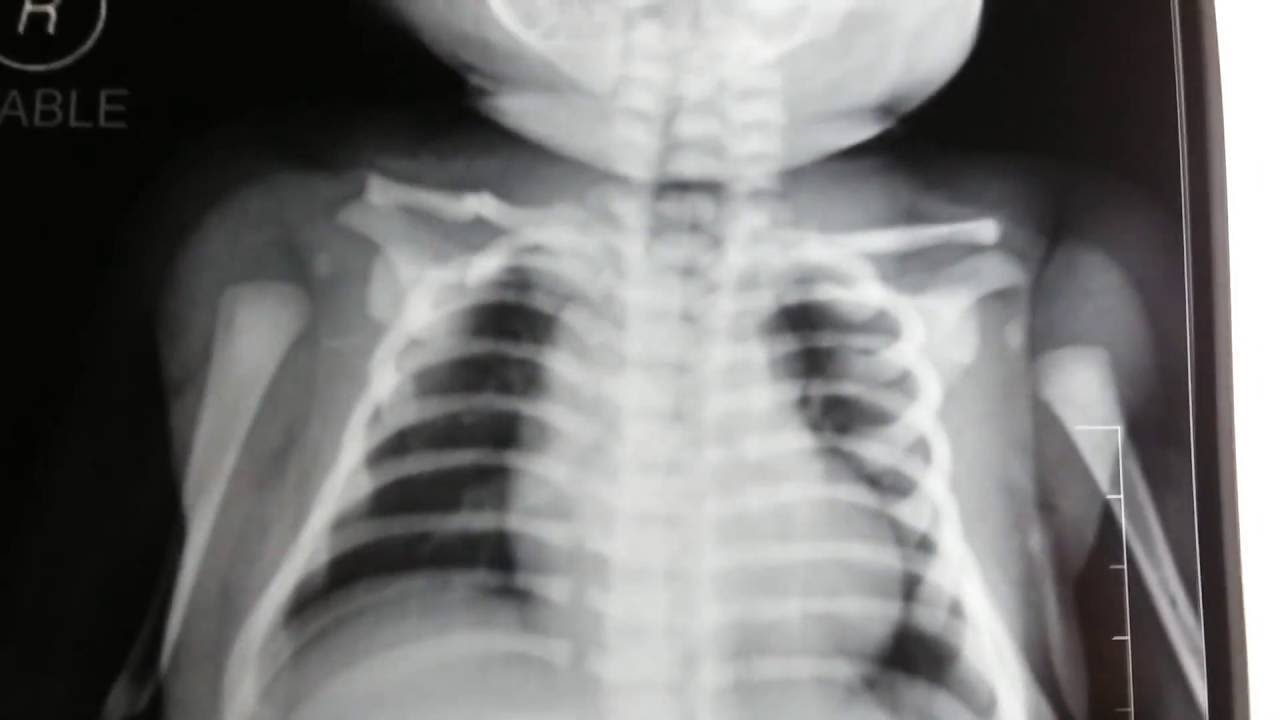

出生后的一大段时间里,可能医生或者家属都还蒙在鼓里,不知道宝宝发生了锁骨骨折。直到有一天,你注意到宝宝一侧上肢不动或少动;给宝宝穿衣服,洗澡或者牵拉宝宝一侧上肢时哭泣,或者发现两边的锁骨位置不一致,或者按压锁骨局部宝宝哭闹挣扎等情况,那肯定是要高度怀疑发生锁骨骨折了。新生儿锁骨骨折的确诊方法主要有两种:X线和超声。

X光诊断

拍摄胸部X光片是判断宝宝是否有锁骨骨折最直接了当的方法。当然,很多宝妈宝爸总担心X光有辐射。从专业角度来说,医院中X光,DR机,CT等,都会释放电离辐射。所以医院通常会有个黄色的标志(如下图,或者提示前方高能!)。这类辐射超过一定的定量,就会损伤DNA,假如细胞不能修复DNA,则可致癌,导致胎儿畸形等危害。

但是,日常医院的X光辐射是极其有限的。比如,手足X光:0.001毫希沃特(mSv),腰椎X光:0.7毫希沃特(mSv),胸部X光:0.1毫希沃特(mSv),腹部X光:1.2毫希沃特(mSv)。普通人超过100毫希沃特(mSv)的辐射量,才会对身体有危害。因而,一般的X光片都不会引起胎儿畸形或影响宝宝发育的。